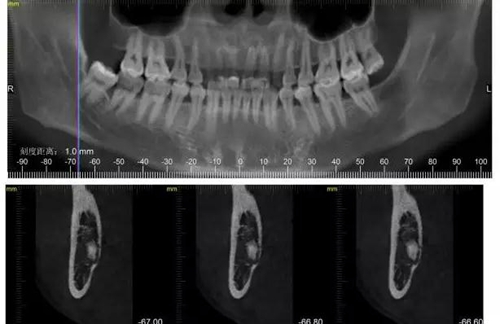

下面CBCT,可以看到兩個牙根的根尖三分之一在神經(jīng)管里面。

下面?zhèn)惹忻?/p>

CBCT神經(jīng)管標(biāo)線,可以看到標(biāo)線不能連續(xù),中間被阻斷。